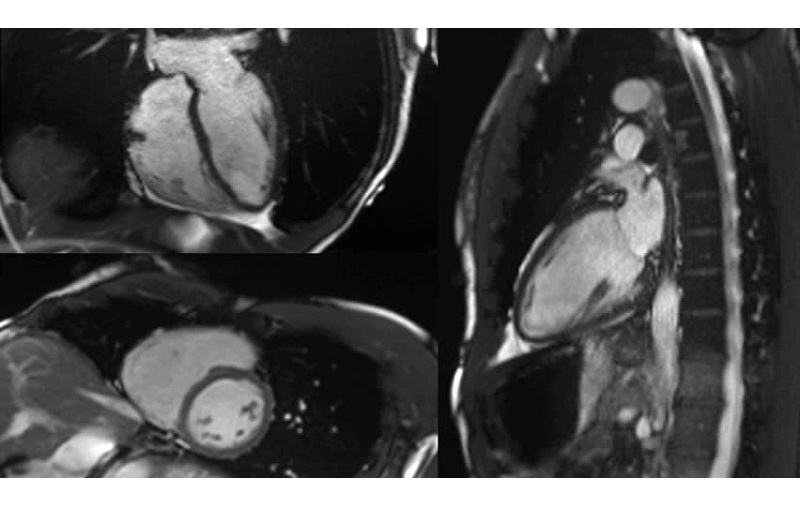

2.4. Ứng dụng chụp MRI trong tim mạch

Chụp cộng hưởng từ (MRI) giúp đánh giá chi tiết về mặt giải phẫu và chức năng của các buồng tim, van tim, cơ tim, cũng như khả năng tưới máu cơ tim. Đối với các bệnh lý mạch máu, MRI đóng vai trò quan trọng trong việc tái tạo hình ảnh hệ thống động mạch, bao gồm động mạch não, động mạch cảnh, động mạch chi, động mạch thận và nhiều mạch máu khác.

Chụp MRI giúp phát hiện nhiều bệnh lý tim mạch